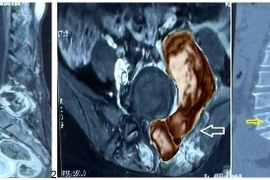

Đau lưng người phụ nữ 48 tuổi không ngờ u cột sống quái ác quay lại

Một số bệnh lý thần kinh ngoại biên khác như u xơ sợi thần kinh cũng có nguy cơ tiến triển ác tính tương tự.